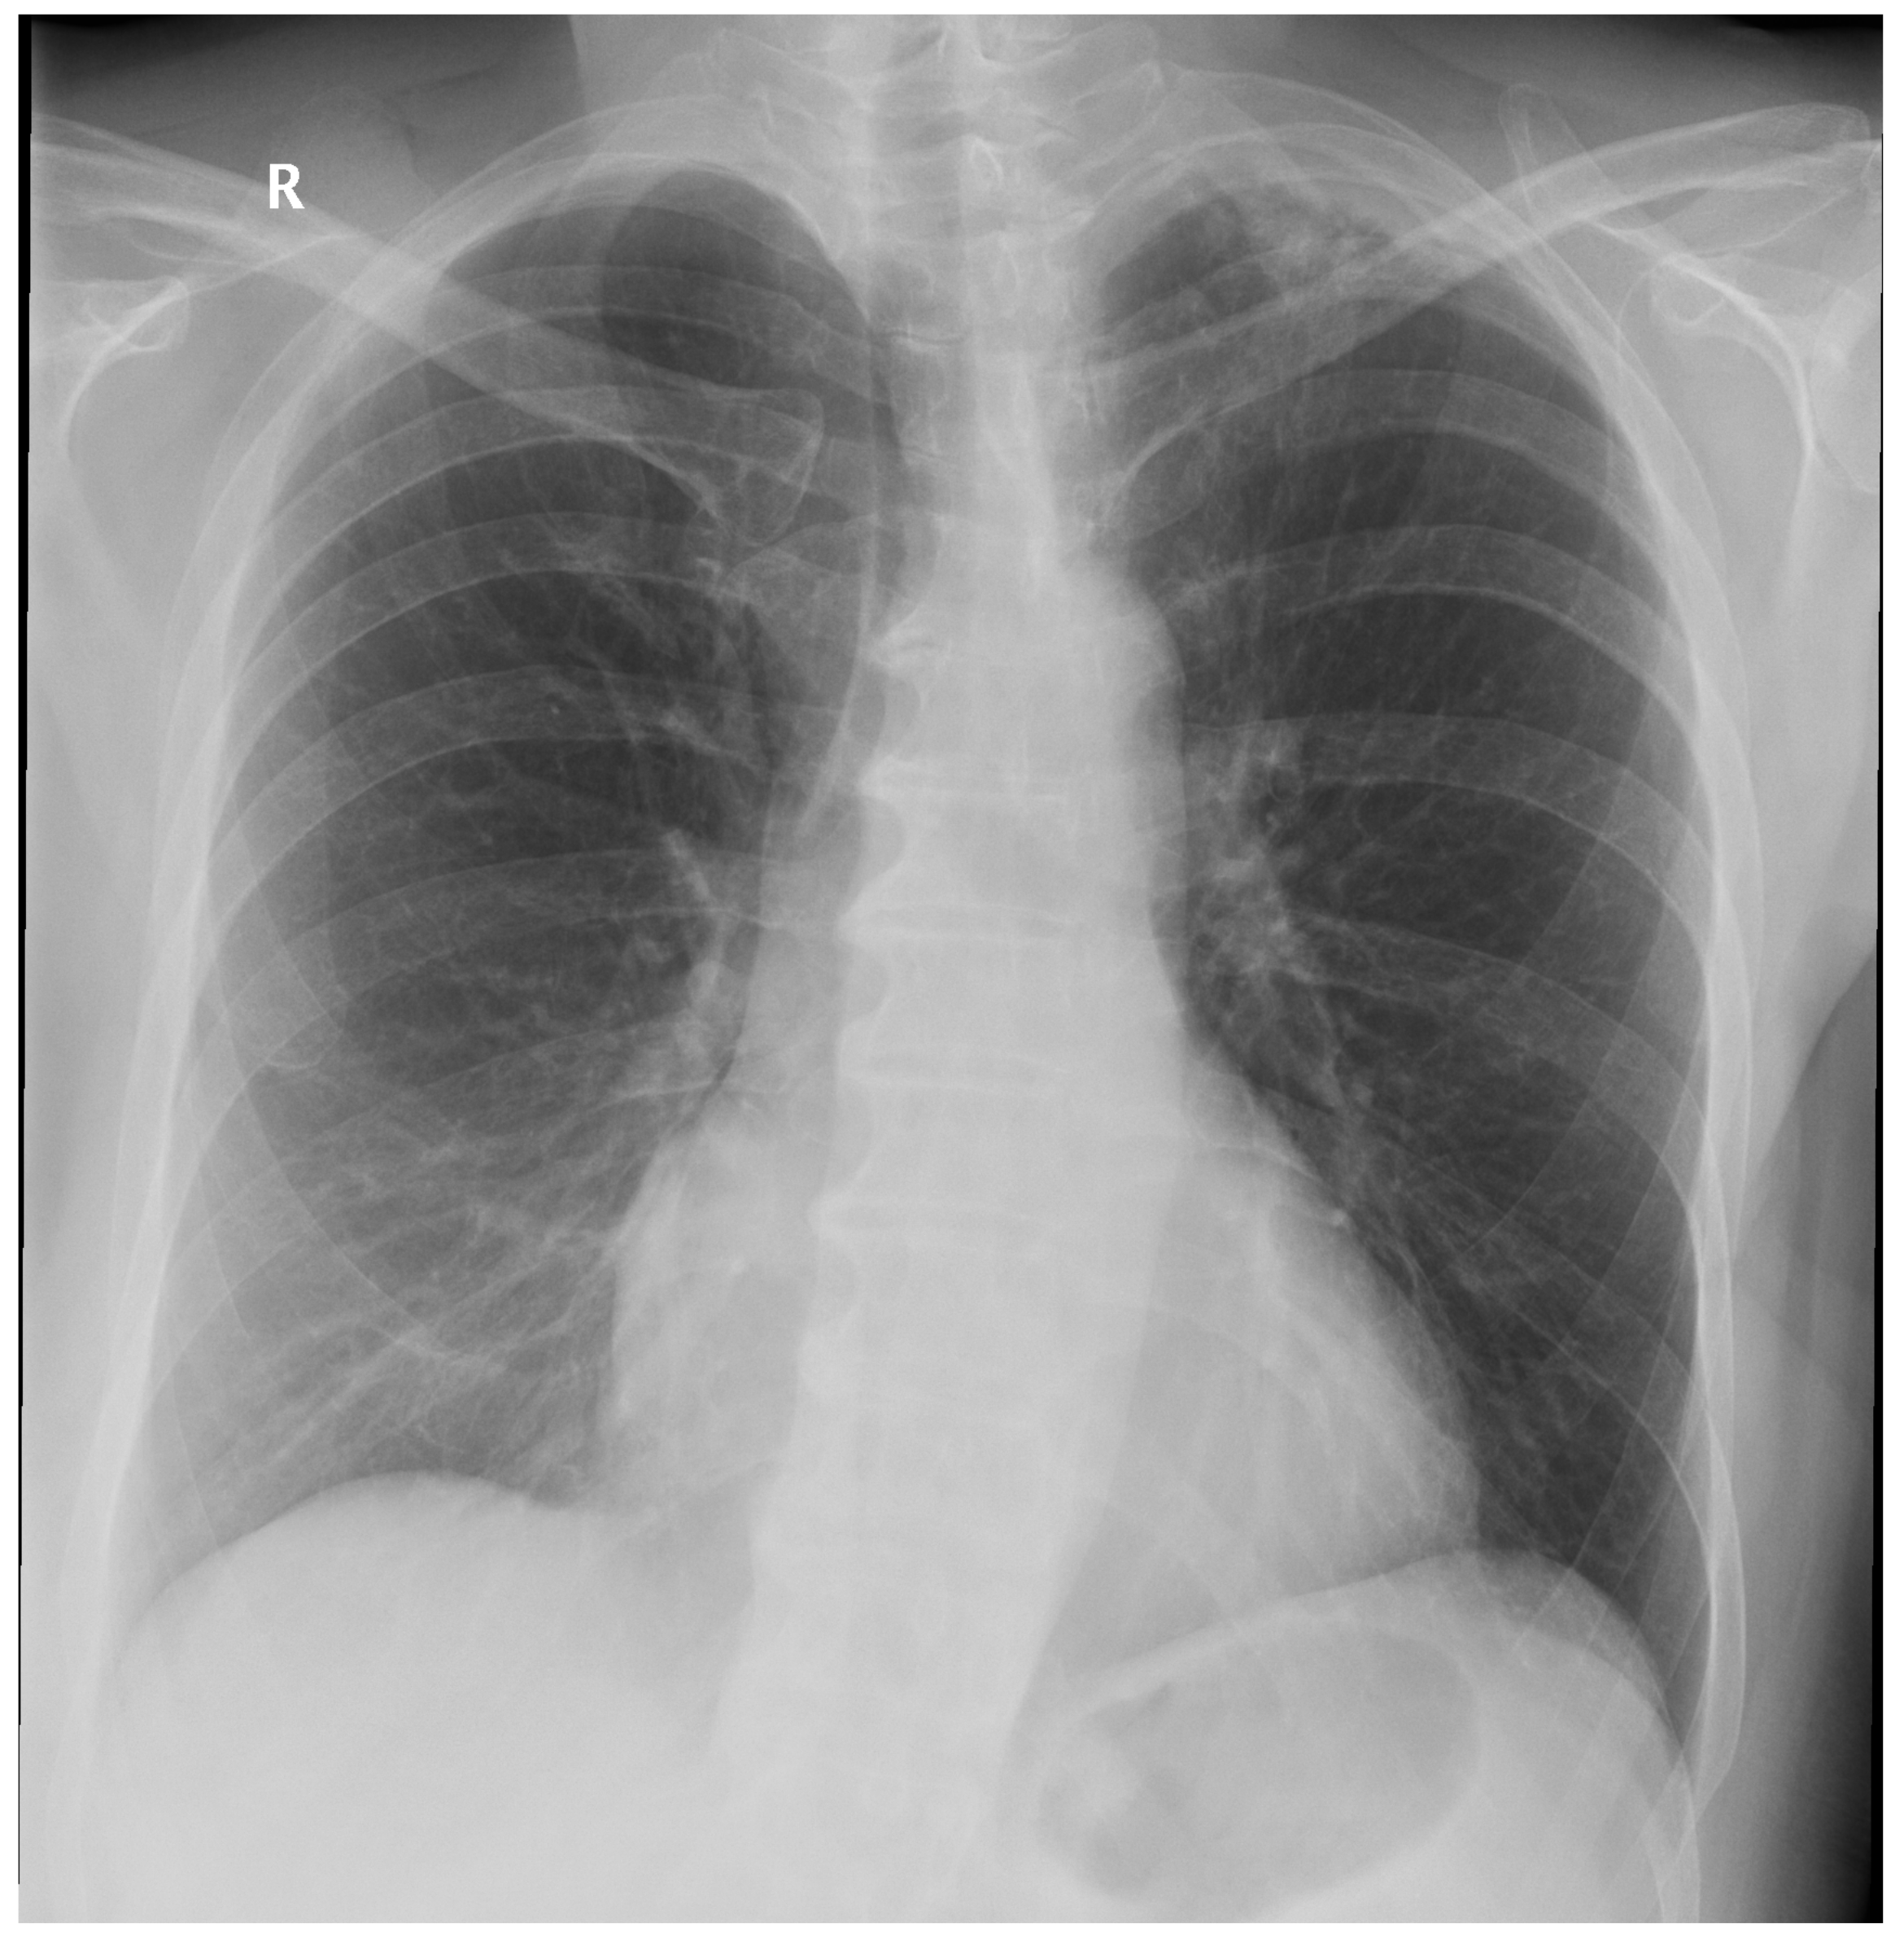

Figure A2.

False Negative image #1 incorrectly classified by DLAD software during the retrospective study. The software failed to detect a lesion in lung parenchyma. Assessed radiologists #5f0 and #24a also incorrectly classified this image as Normal.